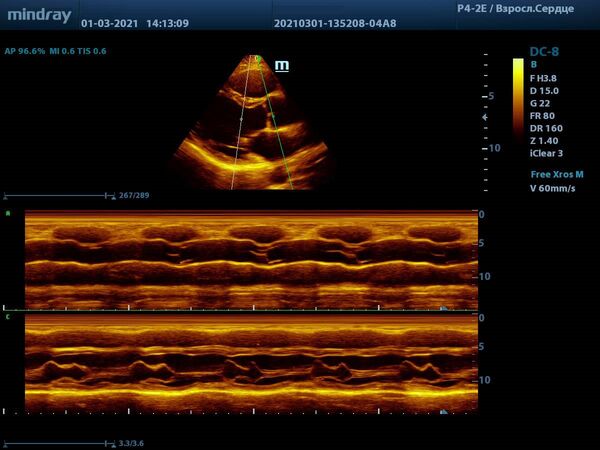

С М-режимом, первым из режимов эхокардиографии, знакомы все. Функцией свободного и анатомического М-режима активно пользуются обладатели машин высокого и экспертного класса. Эти функции используются для оценки створок митрального клапана, формы траектории их движения и амплитуды раскрытия, так же, как и для оценки синуса и полулуний аорты. Современные ультразвуковые диагностические системы компании Mindray, такой как экспертный прибор

Mindray DC-8, способны проводить анализ в М-режиме сразу нескольких срезов до 3-х сечений за один раз. Больше не нужно отдельно выводить срез на уровне концов створок клапана и отдельно уровня синуса аорты. Всё получается нажатием пары кнопок и все готово к измерению.